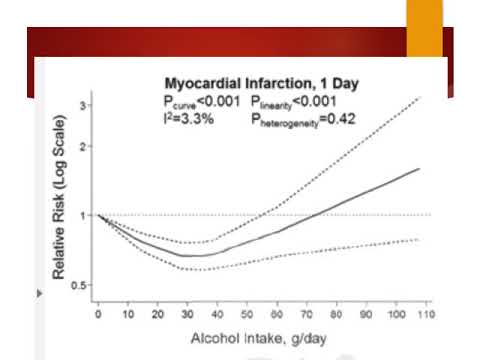

Límites del riesgo de consumo de alcohol. Dra. Ana Laura Mori. Residencia de Cardiología. Hospital C. Argerich. Buenos Aires

Alcohol y riesgo inmediato de eventos cardiovasculares. Dr. Agustín Indavere. Residencia de Cardiología- Hospital C. Argerich. Buenos Aires